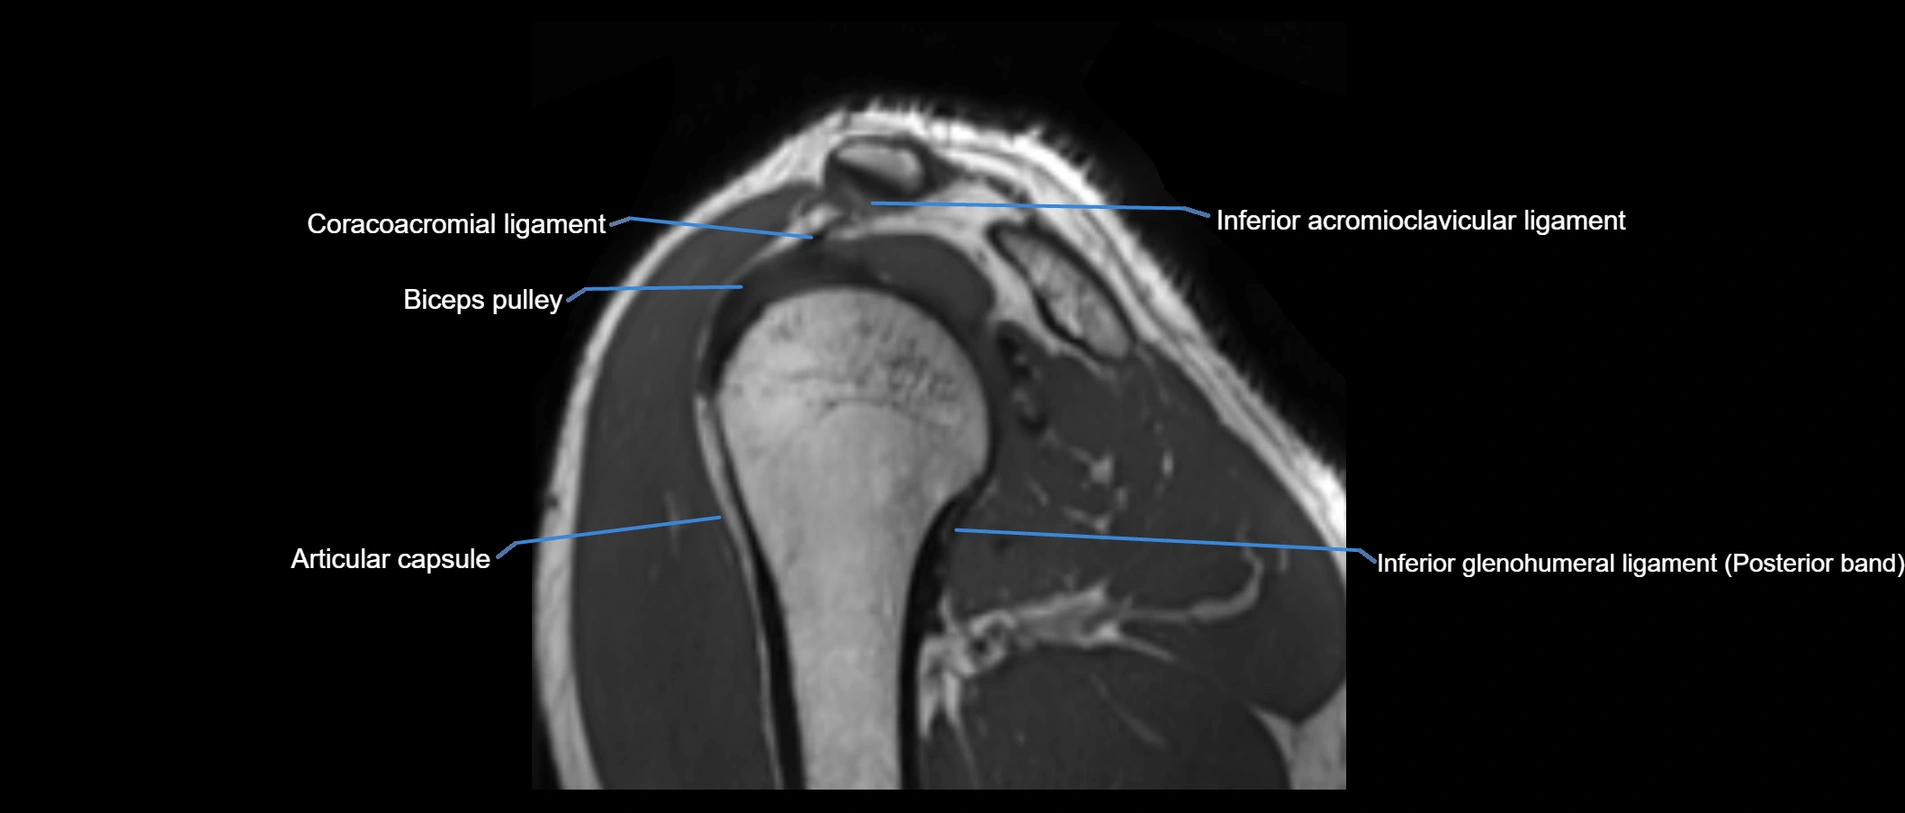

MRI images

image

MRI Appearance

• T1-weighted images:

• Normal ligament: Low signal (dark linear band) spanning acromion to clavicle.

• Surrounding fat planes: Bright, delineating the ligament clearly.

• Marrow of clavicle and acromion: Bright due to fatty content.

• Tears: Discontinuity or irregular thickening with intermediate-to-bright signal.

• Chronic injury: Thinning, fraying, or irregular low-signal fibers with adjacent scarring.

• T2-weighted images:

• Normal ligament: Low signal, homogeneous.

• Partial tear or sprain: Focal hyperintensity or thickening.

• Complete tear: Discontinuity with fluid-bright gap between clavicle and acromion.

• Associated edema: Bright signal in distal clavicle or acromion marrow.

• STIR:

• Normal ligament: Dark linear band.

• Injury or inflammation: Bright hyperintense signal in and around ligament fibers.

• Highlights periligamentous soft-tissue edema, especially in acute trauma.

• Proton Density Fat-Saturated (PD FS):

• Normal ligament: Low signal, uniform thickness.

• Partial tear or sprain: Bright signal or contour irregularity.

• Complete tear: Clear discontinuity with bright signal gap and joint effusion.

• Excellent for assessing joint capsule, coracoclavicular ligaments, and periarticular edema.

• T1 Fat-Sat Post-Contrast:

• Normal ligament: Minimal or no enhancement.

• Inflammation or postoperative repair: Peripheral enhancement due to granulation tissue.

• Chronic degeneration: Irregular enhancement pattern along frayed fibers.